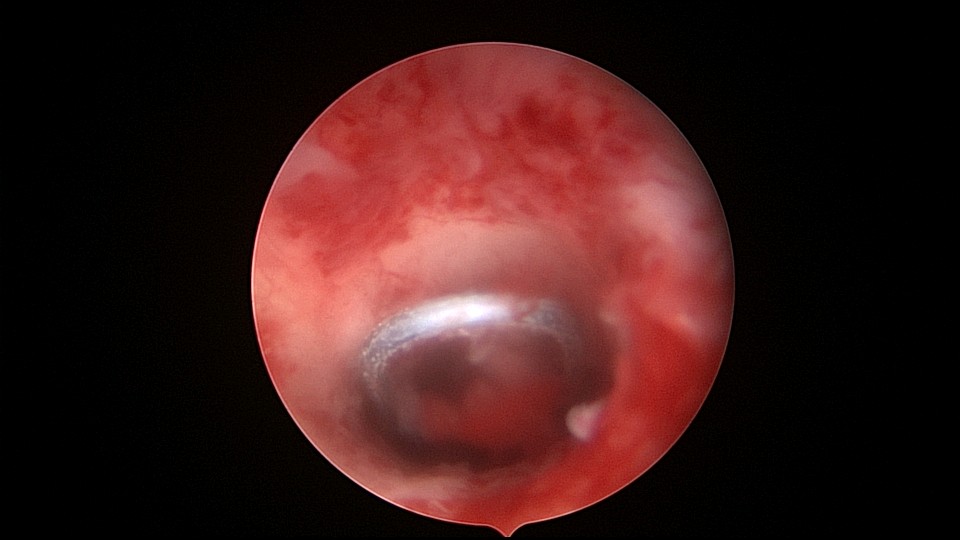

患者48岁,G5P1,剖宫产1次。安环20年,闭经3个月,外院取环失败,形成假道。子宫极度前倾前屈位,宫腔镜见宫颈管上段组织杂乱,左后壁假道,宫腔镜寻找到宫颈内口,艰难进入宫腔,爱母环位置正常,异物钳顺利取出,宫腔无其他异常。